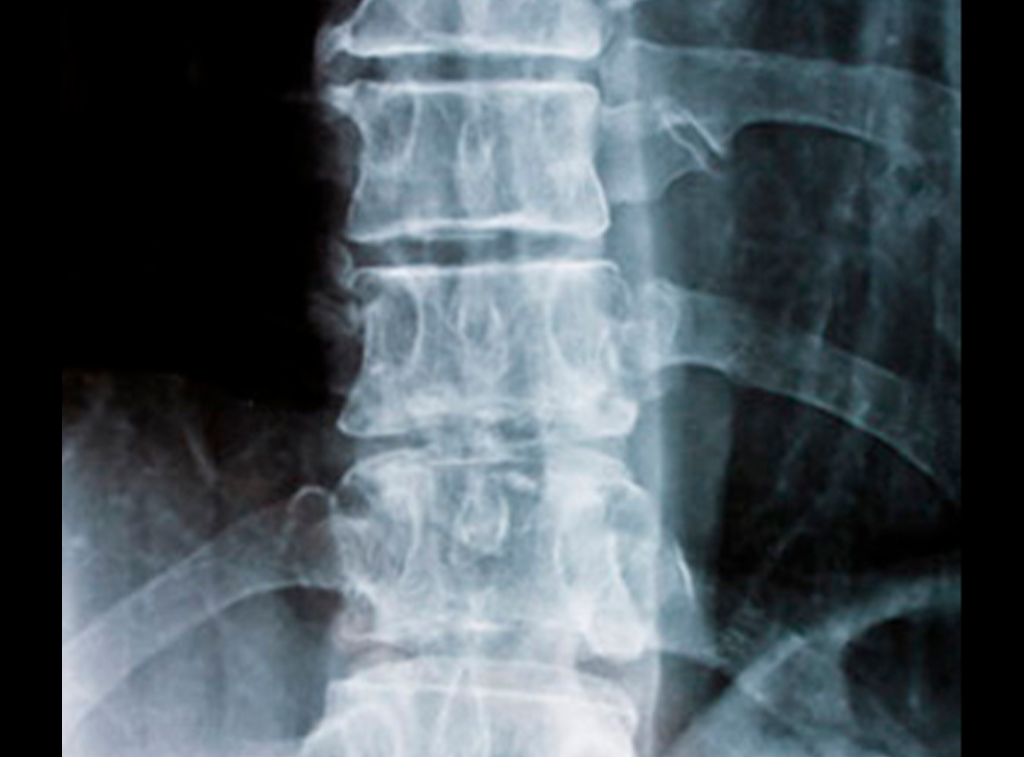

La columna está sometida a mucho estrés a lo largo de la vida, y puede derivar en múltiples molestias, llegando incluso a afectar la calidad de vida.

Algunas de las lesiones de columna más comunes son:

- Hernia de disco

- Fracturas Vertebrales

- Compresión del nervio ciático

- Deformidad por desgaste

Todos ellos pueden ser tratados con cirugía o, en algunos casos, con prótesis.

Desgaste y deterioro

Esta es degenerativa y ocurre cuando hay deterioro en las articulaciones de la columna vertebral.

Inestabilidad espinal

Esto sucede cuando la columna vertebral no está bien apoyada y las vértebras se mueven más de lo normal.